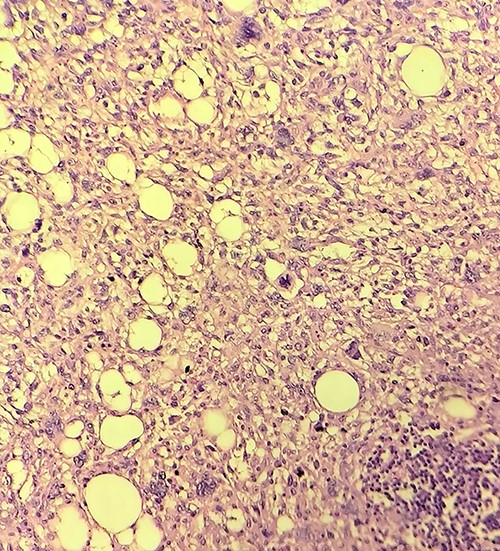

Gross examination revealed large lobulated mass of size 12 cm × 10 cm × 7 cm, weighing 817 g. The cut section showed yellow soft to firm areas with some hemorrhagic areas. Eosin and hematoxylin stain revealed area of lipoblast, pleomorphic cell, mitotic figures with multiple areas of necrosis (Figs 4, 5 and 6). Immunohistochemical reaction showed positivity for S-100 protein, mouse double minute 2 (MDM-2), cyclin-dependent kinase 4 (CDK4) and p16 which helped us differentiate it as dedifferentiated liposarcoma.